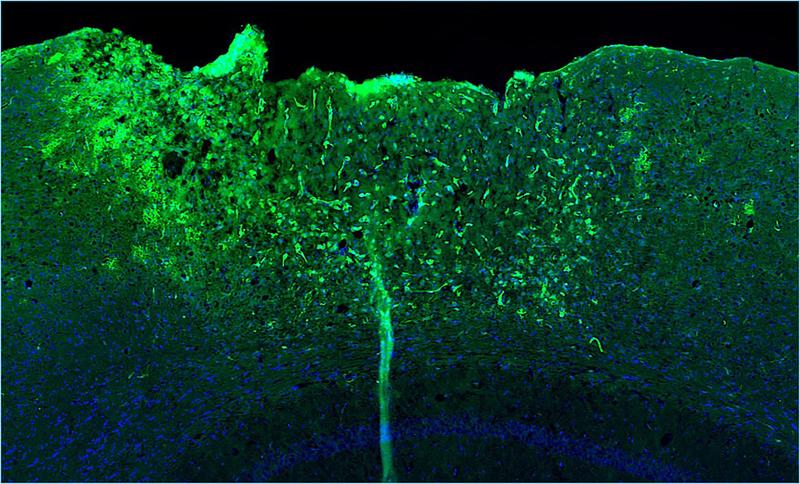

The star-shaped glial cells also play a key role in the wound healing and scar formation process of injured brain tissue. "At the injury/damage site, astrocytes surround the wound core. In this way, they limit further neurodegenerative processes and support healing," explains Professor Leda Dimou. The head of the Department of Molecular and Translational Neurosciences at the Department of Neurology also played a leading role in the study. The researchers found a striking gene expression signature in the immediate vicinity of the insult area indicating a particularly high NF-κB activity in astrocytes. To investigate the influence of NF-κB in more detail, the researchers worked with mouse models. In these, NF-κB was either pre-activated or strongly inhibited in astrocytes. The team wanted to know: Does this modulation improve or worsen healing after traumatic brain injury?

The result was clear: If NF-κB was pre-activated, the immune system reacted more rapidly and stronger to the traumatic injury. This excessive neuroimmune response triggered detrimental inflammatory processes and disrupted both wound healing and scar formation.

"Certain immune cells such as dendritic cells unexpectedly migrated into the wound area. This prevented coordinated scar tissue formation, which ultimately led to neurological deficits," report the study's first authors, Tabea M. Hein and Ester Nespoli. Surprisingly, similar processes occur in the ageing brain. However, when NF-κB was inhibited in astrocytes, single positive effects were observed: Antioxidant defense and mitochondrial function improved, for example. "However, these changes were not sufficient to significantly improve the healing process in general," explain the researchers.